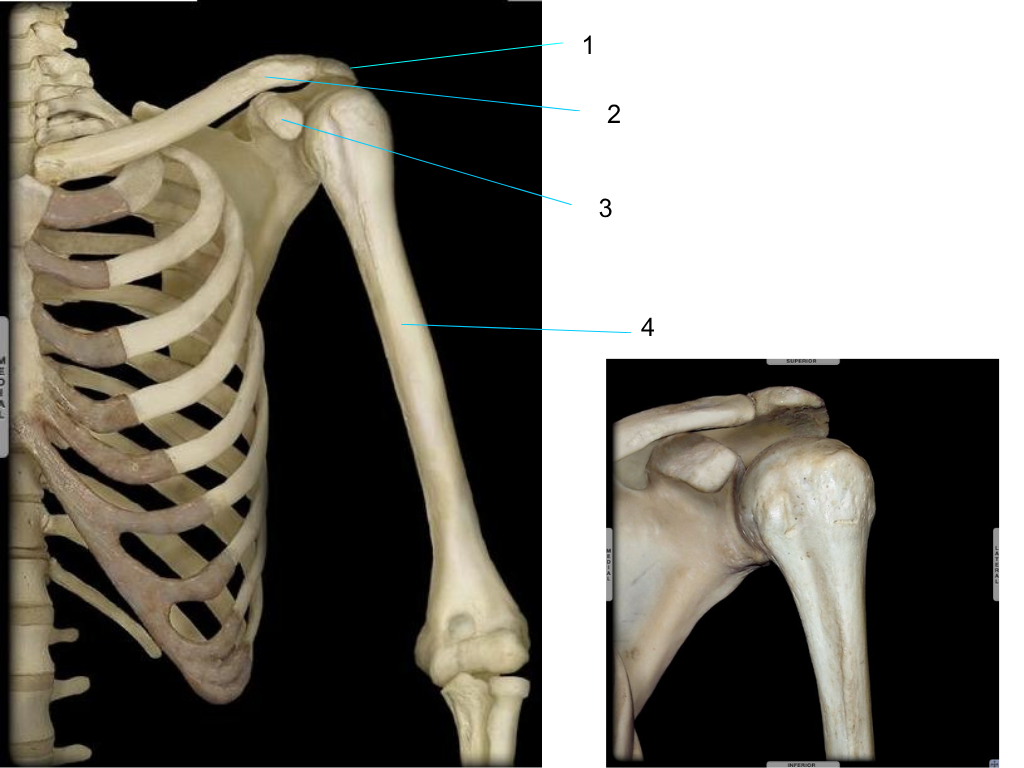

clavicle

what is #1 pointing at?

coracoid process

what is #2 pointing at?

acromion

what is #3 pointing at?

glenoid fossa

what is #4 pointing at?

humeral head

what is #5 pointing at?